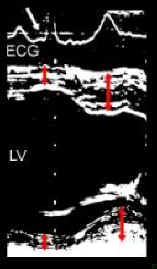

Measurement of end-diastolic (red arrows synchronous with Q wave of ECG) and end-systolic (at maximum systolic wall thickness) left ventricular wall thickness.

Left ventricular wall thickening

PWT= [(end-systolic - end-diastolic) / end-diastolic] x 100 (%)

PWT= 43 - 61 %

IVS= 34 - 50 %